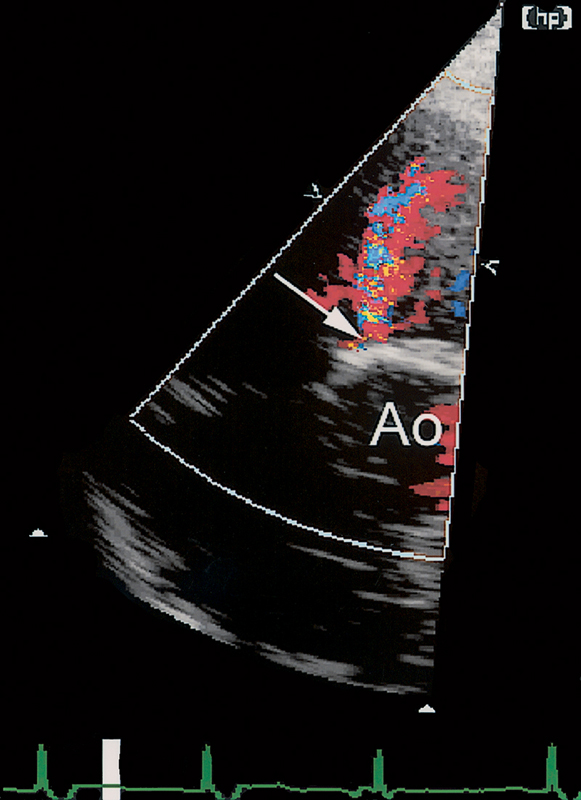

فحوصات تشخيصية لبعض امراض القلب والشرايين التاجية